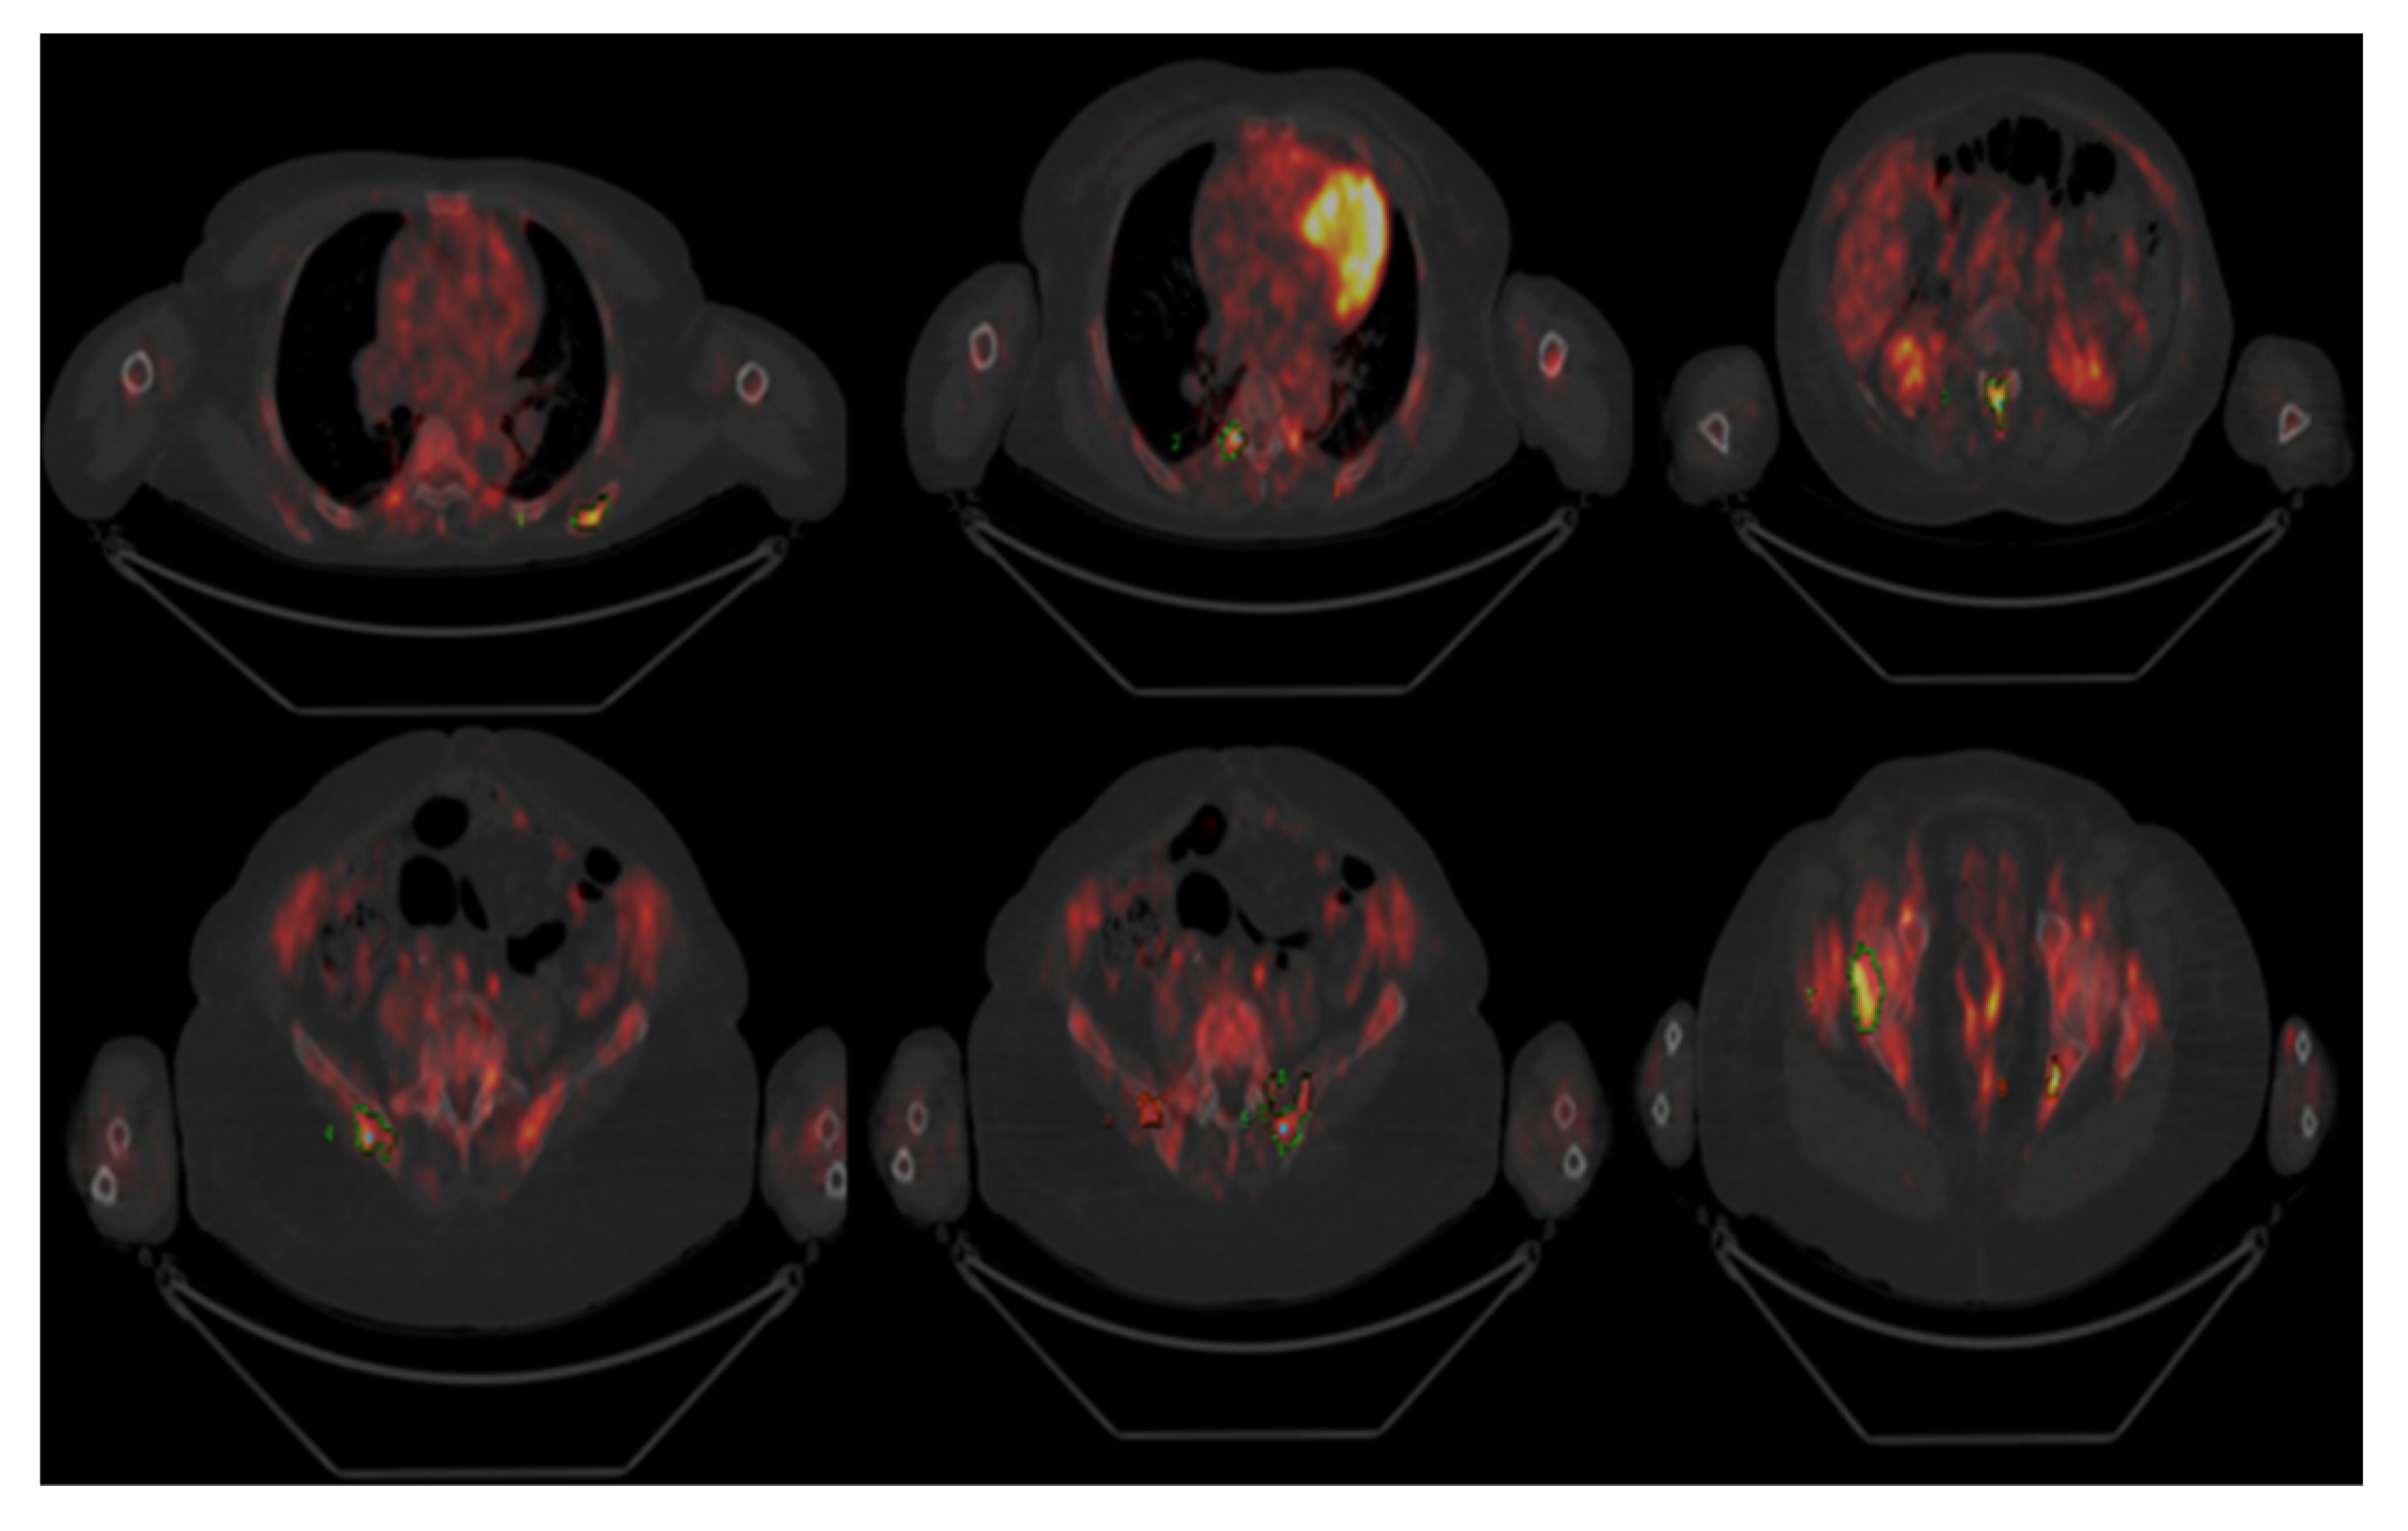

2. Discussion